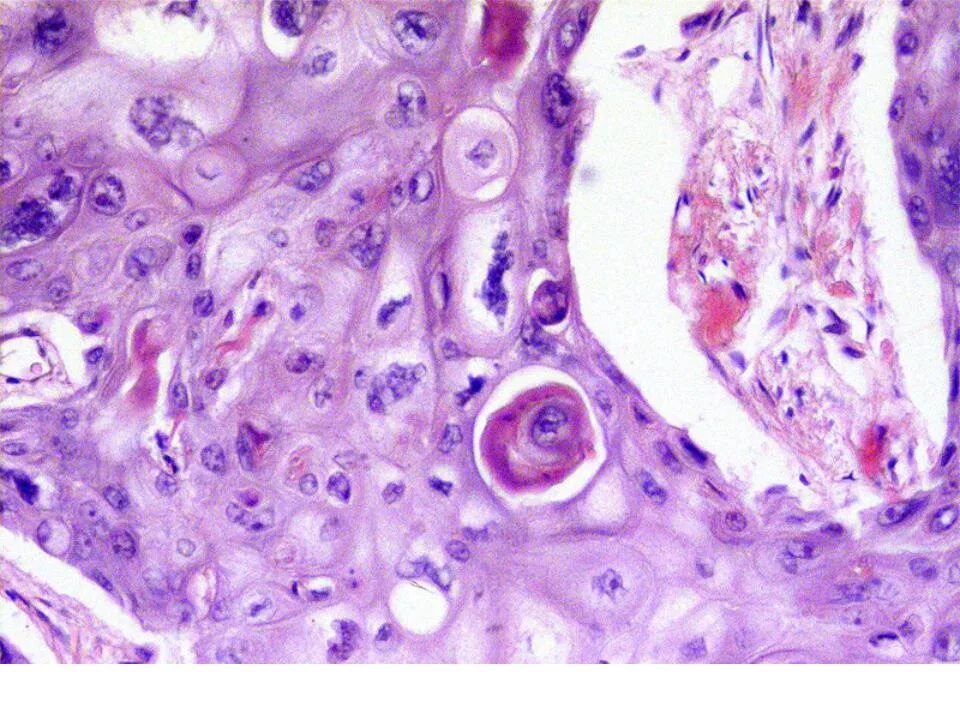

Плоскоклеточная опухоль